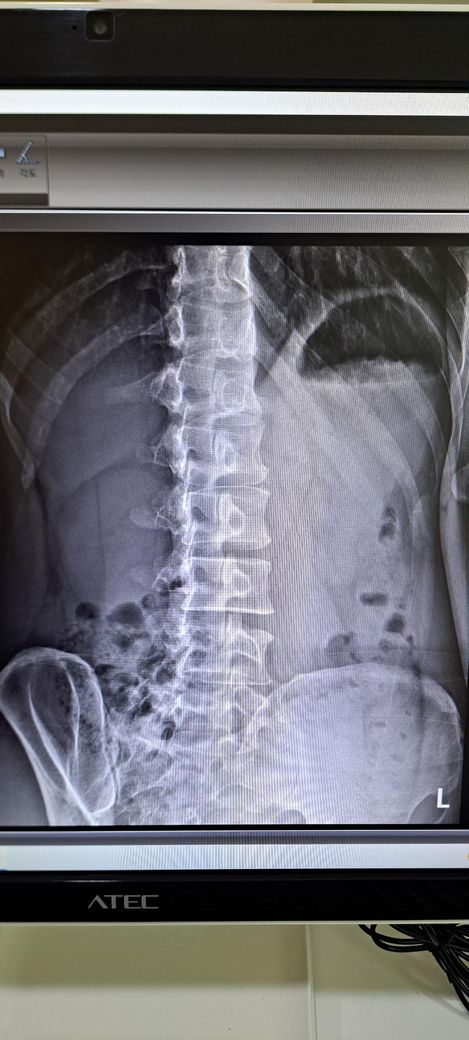

x ray 촬영한 영상인데 골반 틀어짐 및 전방경사 심각한가요? 골반 틀어짐은 어느 쪽을 교정해야 하며 골반 틀어짐 및 전방경사 교정 방법을 알려주시면 감사하겠습니다 .

전방경사 약간 있어 보이나 흔한 범위일 가능성이 크며, 스트레칭.근력운동으로 충분히 교정 가능한 수준으로 보입니다.

허리가 과하게 꺽여 있고 엉덩이는 뒤로 빠져 있는 상태라고 추측되며 측만은 아니라고 생각됩니다.

정면 사진상 골반의 좌우높이 차이가 관찰되며, 이는 대퇴골의 위치변화와 연관되어 보입니다. 측면 사진에서 요추의 곡선이 다소 꺾여 있는 양상이 보여 골반 전방경사 가능성이 큽니다. 정면 영상에서 척추가 일직선이 아니라 완만한 S자 형태로 휘어있는 측만 소견이 보입니다. 심각한 수준은 아니나 지속적인 관리가 필요한 상태입니다. 측면 사진상 경추의 커브를 보면 일자목 상태입니다. 골반이 높은쪽의 근육은 이완시키고, 낮은쪽과 약해진 둔근, 복근을 강화하는 운동이 필요합니다. 전방경사 완화를 위해 장요근 스트레칭과 프랭크 같은 코어 운동이 효과적입니다. 흉쇄유돌근 스트레칭과 더불어 등 근육을 강화하여 어깨를 펴는것이 급선무입니다.

전방경사의 경우 현재 요추는 요추전만이 잘 만들어져있기 때문에 골반의 경사가 문제가 되는 상태가 아닌걸로 판단됩니다.